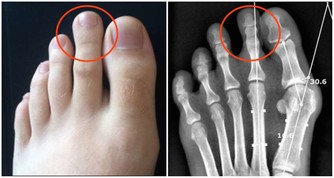

4、腳掌紋路增多

中醫認為,肝主藏血,肝臟每天會分解血液中的毒素或代謝產物,當肝臟受損時,其解毒能力也會有所下降,血液健康也可能受到一定影響。腳距離心臟較遠,如果腳掌紋路增多且變得明顯,要注意腳下保暖和保養肝髒了。

另外,女性們腳趾腹側面如果出現很深的粗紋,或者有針孔狀,需警惕婦科問題,例如內分泌失調、月經失調等。